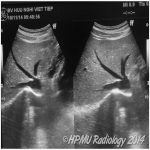

Sỏi tuyến nước bọt (Salivary duct stone) là sự tích tụ các khoáng chất trong ống dẫn từ các tuyến nước bọt. Sỏi được tạo ra từ các muối Calcium và có kích thước thay đổi. Chúng làm nghẽn một phần hay toàn bộ ống tuyến. Thường gặp ở người trên 40 tuổi, nữ gấp 2 lần nam giới…